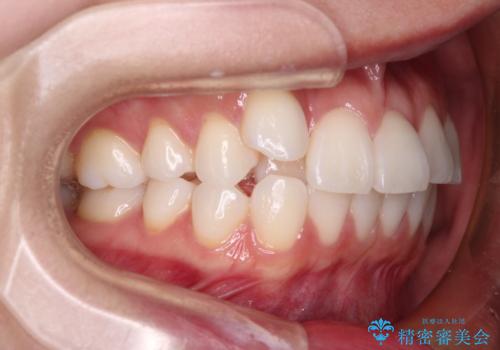

- 八重歯と、それによる正中のズレを気にして来院された患者様です。

口元の突出感は気にしていなかったため、上顎の左右第一小臼歯を抜歯することで、八重歯の解消と上顎の正中を改善していくこととしました。